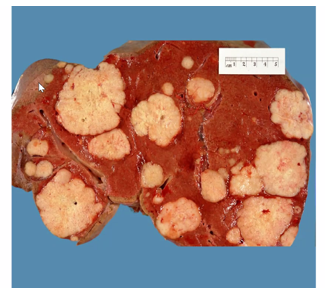

describe the specimen

Very red and haemorrhagic

Polypoid, raised

Lobulated but smooth

Doesn’t look like invading wall – could be pedunculated with stalk

Adenoma – benign polyp that is dysplastic

Have malignant progression if get larger

Very common